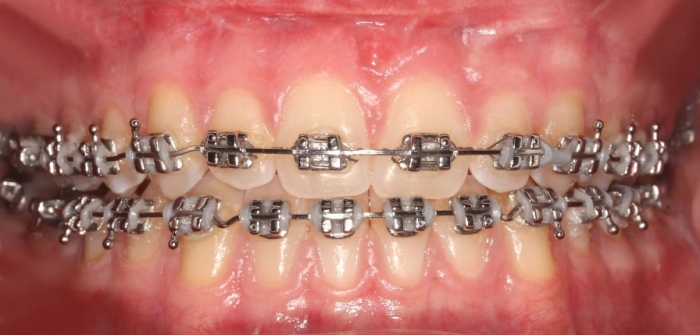

Mordida após a cirurgia realizada em 2016 - Clínica Cliniface

Mordida após a cirurgia realizada em 2016